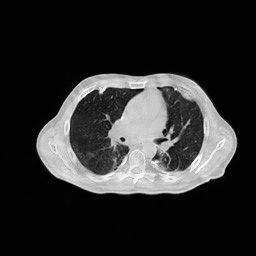

The aforementioned neural networks are implemented in Python with the PyTorch library. The RMSProp algorithm serves as the optimizer, with a learning rate set to , which decreases by a factor of every iterations. The hyperparameters utilized in the RBP-DIP framework are assigned the values , and . Images from LIDC-IDRI [3] (The Lung Image Database Consortium image collection) dataset are used in our experiments.

4.3 Few-View CT Reconstruction

In this section, the reconstruction performance of our proposed framework under few-view conditions will be tested. For the parallel-beam and fan-beam geometry, the number of views increases from to , uniformly distributing from to and to respectively. Such settings provide a complete benchmark of reconstruction performance, ranging from extremely sparse to relatively complete, full-view CT reconstruction. The experiment results are shown in Fig.5. Additionally, the ground truth, few-view ( views), and full-view ( views) CT reconstruction results of different methods are shown in the first and third rows of Fig.7 (parallel-beam, LIDC-IDRI dataset), and Fig.8 (fan-beam, LIDC-IDRI dataset).